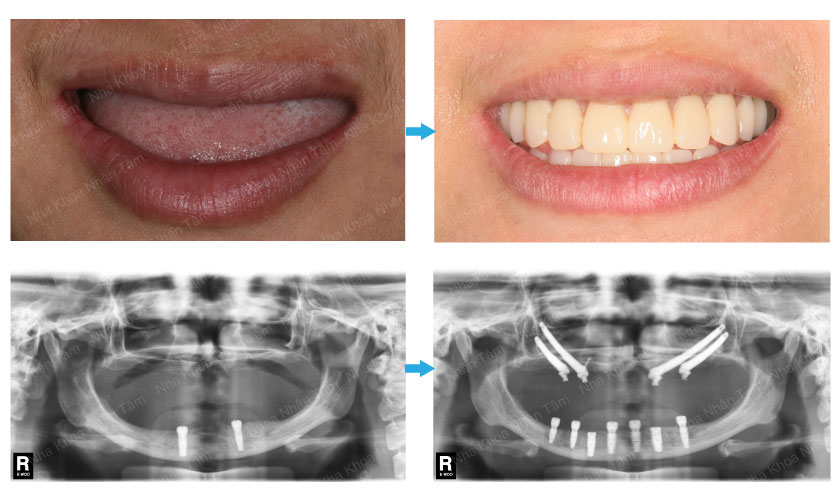

Khách hàng trước và sau khi trồng răng sứ tại nha khoa Nhân Tâm